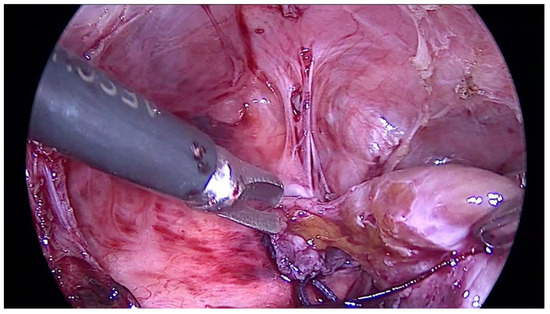

| Four years and six months old | The second thoracoscopy—removing the part of ‘ingrowing liver’ and suturing a diaphragmatic defect |